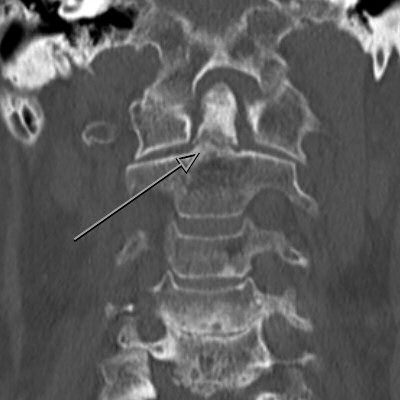

Exempel på dens-fraktur typ 3. Behandlades med halskrage i 12 veckor.